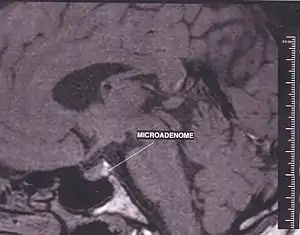

آدنوم هیپوفیز تومورهایی هستند که در هیپوفیز رخ می دهند، آدنوم های هیپوفیز اصولاً به سه دسته تقسیم می شوند، آدنوم خوش خیم، آدنوم بدخیم و کارسینوما. ۳۵ درصد بیماری های این دسته از تومور ها را آدنوم بدخیم و اکثرشان را آدنوم خوش خیم تشکیل می دهند و تنها ۰.۱ تا ۰.۲ درصد را کارسینوما تشکیل می دهد. آدنوم های هیپوفیز ۱۰ تا ۲۵ درصد تومور های داخل-جمجه ای را تشکیل می دهند.[1][2]